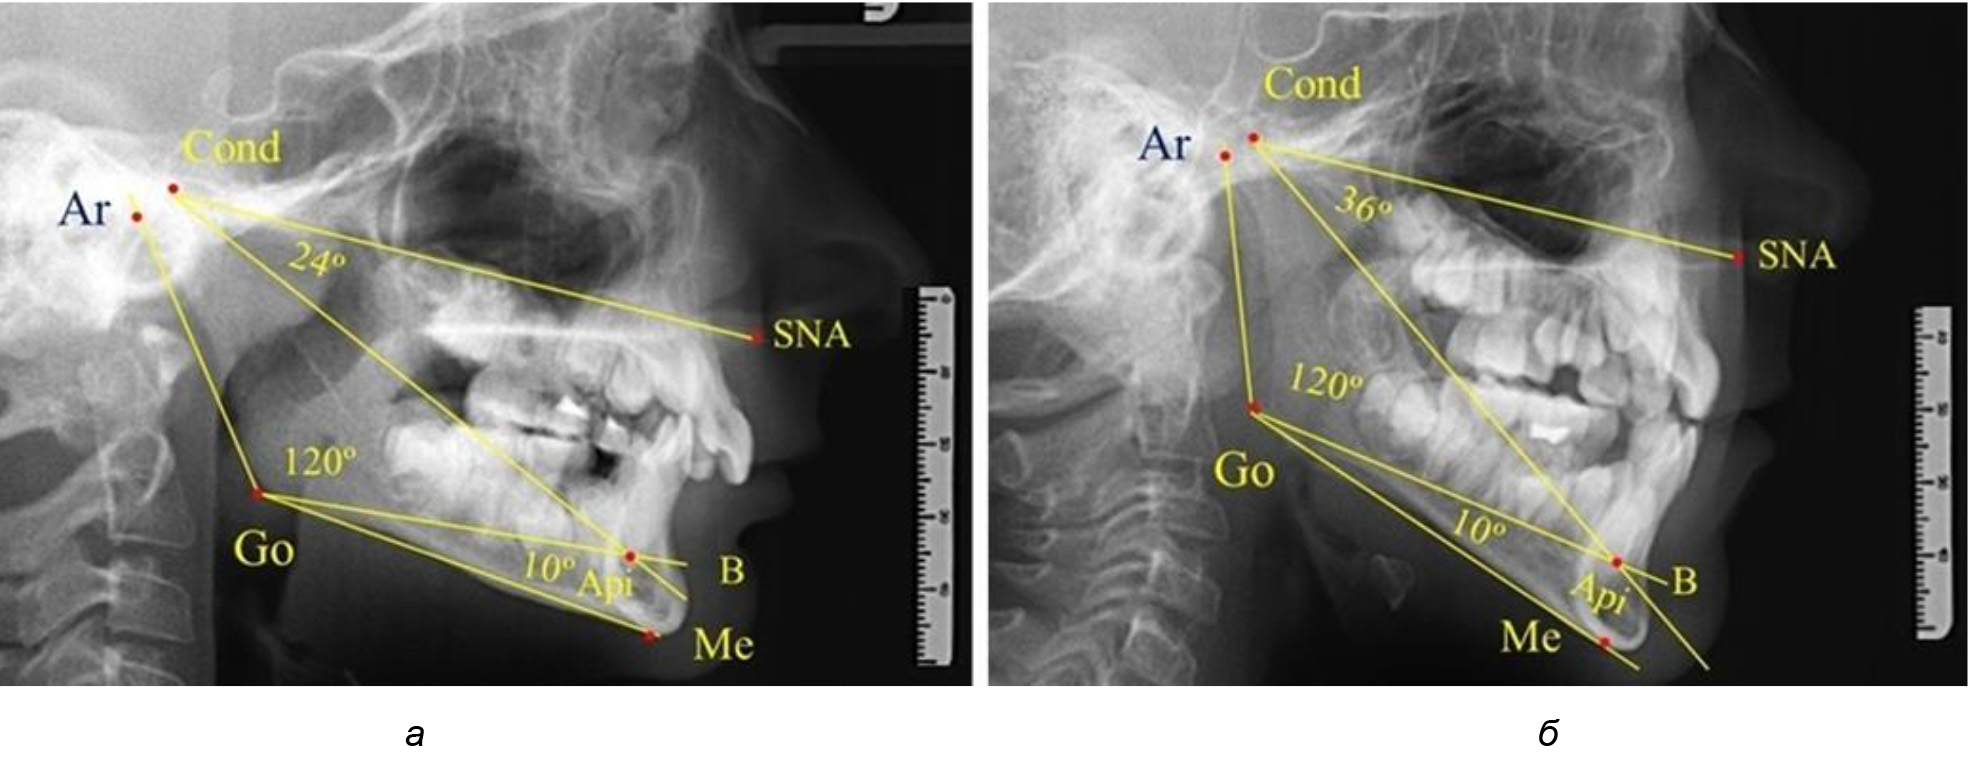

При анализе 16 рентгенограмм с аномалиями окклюзии в вертикальном направлении были выявлены признаки изменения основного гнатического угла. Так, для гнатических аномалий глубокой резцовой окклюзии/дизокклюзии (9 человек) отмечалось уменьшение угла гнатической части лица, величина которого была менее 26°. В то же время для гнатических аномалий (7 человек) вертикальной резцовой дизокклюзии («открытый» прикус) определялось увеличение угла гнатической части лица, который превышал значения в 33° (рис. 7).

Рис. 7. Варианты ТРГ при глубоком прикусе (а) и при открытом прикусе (б)

На представленных клинических примерах, несмотря на различия параметров основного угла гнатической части лица, определялись однотипные варианты угла нижней челюсти Ar-Go-Me и его составных частей Ar-Go-Api и Api-Go-Me.

Таким образом, установлено, что основным показателем, определяющим оптимальные параметры гнатического отдела лица, является угол гнатического отдела лица, образованный пересечением линии, соединяющей точку передней носовой ости с верхней точкой суставной головки SNA-Cond, и линией, отходящей от суставной точки до верхушки корня нижнего медиального резца Cond-Api. Средняя величина угла гнатического отдела SNA-Cond-Api составляла (29,96 ± 0,84)° при физиологической окклюзии постоянных зубов и практически была аналогичной во все периоды онтогенеза.